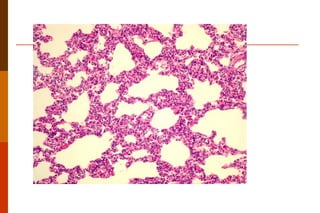

Microscopicamente : destruição dos septos alveolares, resultando em dilatação dos alvéolos e ductos alveolares, além da perda do componente elástico. DPOC -  enfisema pulmonar  Alveolos normais enfisema

Microscopicamente : destruiçãodos septos alveolares, resultando em dilatação dos alvéolos e ductos alveolares, além da perda do componente elástico. DPOC - enfisema pulmonar Alveolos normais enfisema

Enfisema e parênquima pulmonar normal.